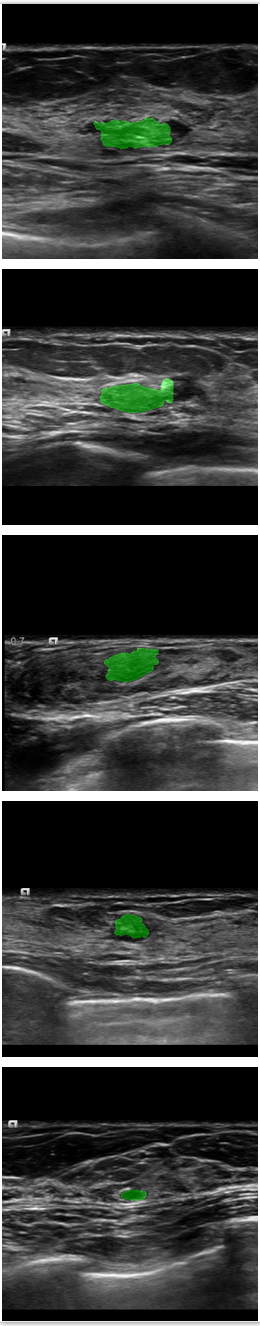

Refer to caption

Figure 7: Comparison of SPCGAN and other segmentation methods of malignant lesions.(a) shows original image of malignant lesions, (b) shows the manual annotation, (c) shows the result of SPCGAN ,(d), (e) and (f) show results from FCN(ResNet), Mask R-CNN and the level set method.

The examples given in Fig.7 correspond to the segmentation results of our SPCGAN, FCN(ResNet), Mask R-CNN and the level set method from malignant lesions. The FCN(ResNet) tends to oversegment the cancer when there is posterior shadowing, especially for the lesion in the first row. SPCGAN shows relatively more robust performance compared to FCN(ResNet), Mask R-CNN and the level set method.